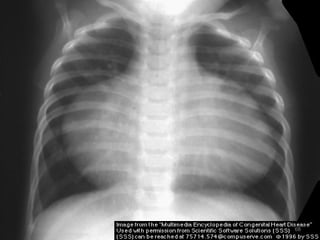

Cyanotic CHD…

Diagnosis

CXR - Narrow base & uplifted apex

- A boot or wooden shoe

- decreased pulm. vascularity

- Right side aortic arch in 20%

ECG

Echocardiography